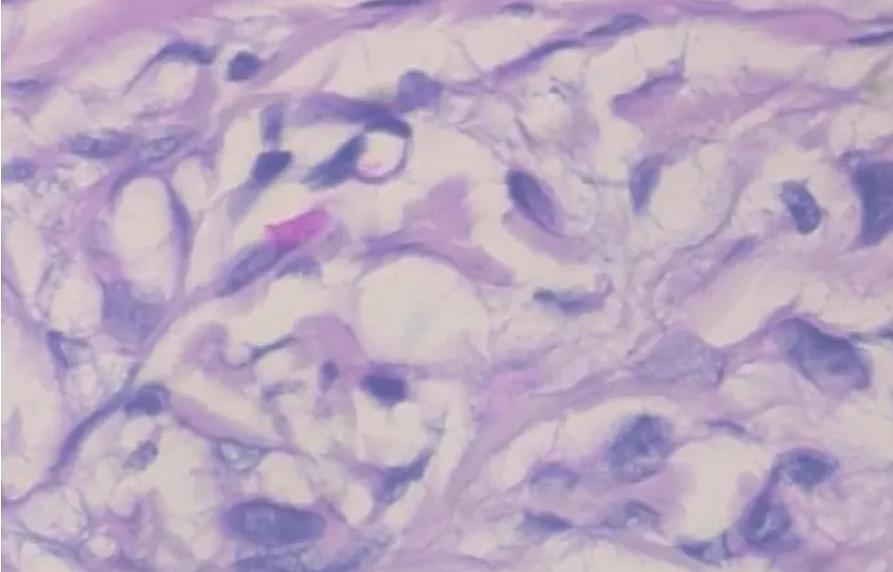

3.2 病变样本

在这个博客中,学长我演示了如何使用卷积神经网络和迁移学习从一组显微图像中对良性和恶性乳腺癌进行分类,希望对大家有所帮助。